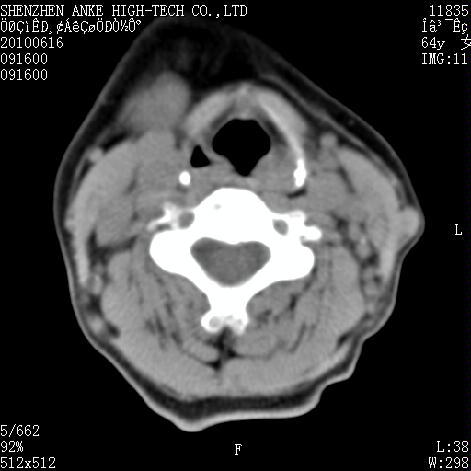

标题: CT27132:患者女,64岁,颈部及全身多处包块,现觉吞咽困难4 [打印本页]

标题: CT27132:患者女,64岁,颈部及全身多处包块,现觉吞咽困难4

右侧甲状腺占位,肿瘤可能性大,癌

右侧甲状腺癌伴右颌下腺淋巴结转移

右侧甲状腺癌伴淋巴结转移

右侧甲状腺癌伴淋巴结转移可能性大

淋巴瘤可能,再向下扫描胸部看纵隔内淋巴结

右侧甲状腺癌伴淋巴结转移可能性大。

右侧甲状腺癌伴右颌下腺淋巴结转移!建议增强!